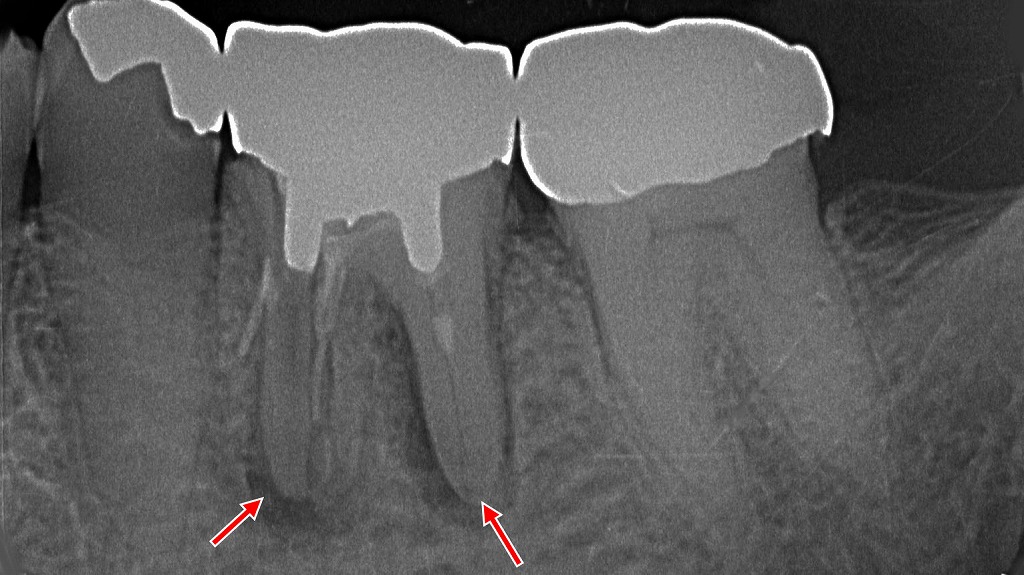

🔍視診で気づける主な特徴

- 抜歯窩が大きく開いている

→ 通常は血餅でふさがる部分が、ぽっかりと開いた状態になっています。 - 抜歯部位が白っぽく見える

→ 血餅がなくなり、骨が露出して白く見えるのが典型的です。 - 黒や赤ではなく白色の抜歯窩

→ 正常なら赤黒い血餅が見えるはずですが、白色は異常のサインです。 - 穴が乾燥し、悪臭や汚れがある

→ 食べかすや細菌によって腐敗臭がすることもあります。